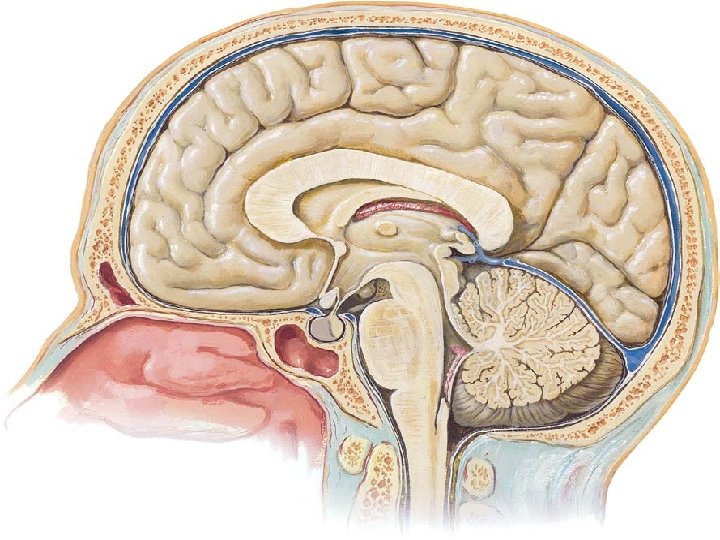

Gross anatomy of the pituitary gland The average weight of the pituitary gland at birth is about 100 mg. Rapid growth occurs in childhood, followed by slower growth until the adult weight (approximately 500– 600 mg) is attained in the latter part of the second decade. The adult hypophysis measures approximately 10 mm in length, 10 to 15 mm in width, and about 5 mm in height

Although the adult hypophysis typically measures less than 1 cm in its greatest dimension and weighs less than 1 g, its small size gives a wrong idea about its importance and complexity Embryogenesis of the pituitary gland The pituitary gland originates from two discrete parts of the developing embryo , (neural & epithelial) The ant. Lobe develop from the roof of the mouth(epith. )and called adenohypophysis The post. Lobe develop from the brain(neural)called neurohypophysis

The pituitary gland derives its blood supply from two groups of arteries. The superior hypophyseal artery (SHA) primarily supplies the anterior lobe, whereas the inferior hypophyseal artery (IHA) is primarily related to the pars nervosa. The SHA can arise from the supraclinoid portion of the internal carotid artery (ICA) or from the posterior communicating artery, whereas the IHA arises from the meningohypophyseal trunk, a branch of the cavernous segment of the ICA

The oculomotor nerve, trochlear nerve, and first two divisions of the trigeminal nerve are embedded in the lateral wall of the cavernous sinus, lying between the endothelial lining and the dura mater, whereas the abducens nerve is contained within the sinus itself